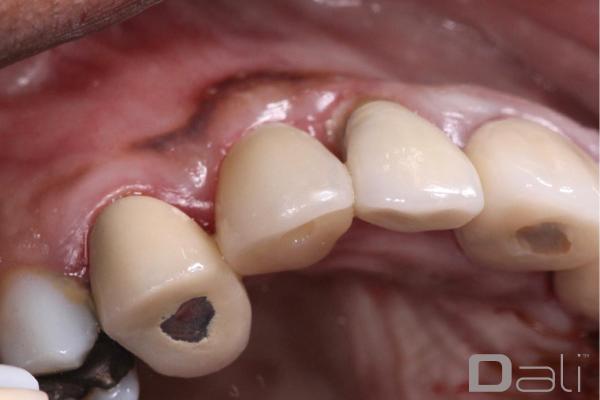

DALI Flex graft has the ability to stay in position and maintain space well. You can see from the post-operative pictures below, taken 2 years after the procedure, that the ridge contour and the tissue profile are ideal. Clearly, the DALI Flex Graft integrated well into the surrounding bone and tissue in a very healthy, and stable manner.

Initial Case Photos

Following a GBR at the time of implant placement, a buccal ridge deficiency persisted. Surgical uncovery of the implant to expose the cover screw revealed successful bone regeneration around the implant, but a residual lack of ridge contour. Instead of using a traditional particulate graft covered with a resorbable membrane, a “flexible bone graft” sheet, DALI Flex Graft, was placed over the buccal plate to augment the buccal contour. Because the graft comes hydrated, it is easy to handle and adapt to the defect location. The flap was then pulled over the graft and adapted around the healing abutment. Following 6 weeks of healing, we see nice healing and an obvious increase in the facial contour.